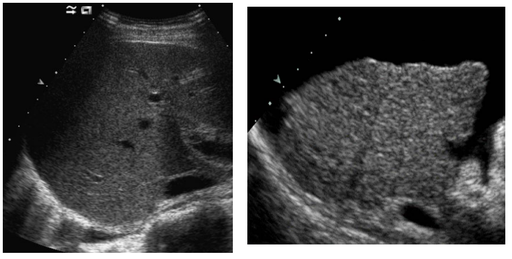

Contraste digestif en radiologie adulte

DANSE E. - UCL

Digestif MASTER 1